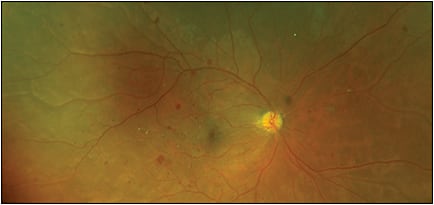

FIGURE 2. Severe nonproliferative diabetic retinopathy with DME (California ultra-widefield imaging by Optos).

Image courtesy of Seenu Hariprasad, MD